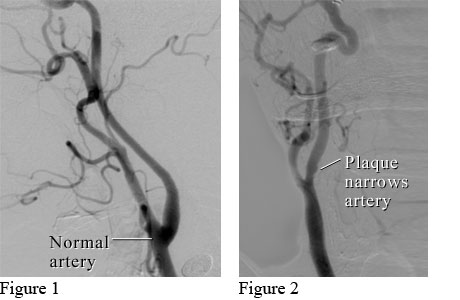

Angiogram of the carotid artery